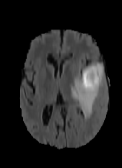

The dataset’s MR images are preprocessed so that the skulls and neck regions are removed. The images are aligned and co-registered to correct any head tilt or mismatches between MR modalities. Each voxel in the image corresponds to of brain tissue. Figure 5 illustrates a 2D axial input MR Images sample and the corresponding ground truth. The input images (a-c) show the different MR modalities: FLAIR, T1CE, and T2 images. The ground truth consists of peritumoral edema (ED) marked in light grey given by an intensity value of , enhancing tumor (ET) represented as a white region with as an intensity value, and the non-enhancing tumor (NET) and necrotic core region (NCR) as dark grey with an intensity value of . The models are evaluated as enhancing tumor (ET), tumor core (TC), and whole tumor (WT). The tumor core corresponds to NET/NCR and the enhancing tumor region. The whole tumor corresponds to all three tumor regions put together. The research aims to learn the ED, NET/NCR, and ET regions.